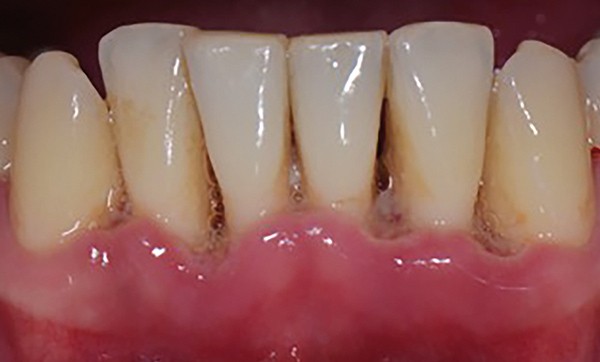

Il s’agit d’une inflammation aiguë, douloureuse, à progression rapide, de la gencive (gingivite nécrotique) susceptible de progresser vers le parodonte profond et d’évoluer rapidement vers la perte d’attache (parodontite nécrotique).

On observe des lésions nécrotiques au niveau des papilles interdentaires, associées à une décapitation des papilles.

Un enduit blanchâtre pseudomembraneux est présent au collet de la gencive.

La gencive est rouge, œdémateuse, friable, saignant au moindre contact.

Des dépôts de plaque sont notés, ainsi qu’une halitose.